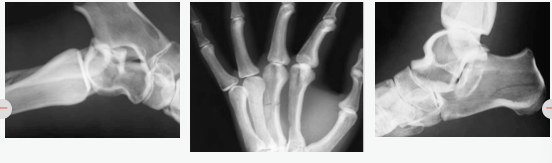

-设计用于成像任何临床视图(正位,斜位,侧位,蛙腿等)

胳膊 左臂桡骨、尺骨移位性骨折

左手第三和第四掌骨骨折

胫骨近端骨折伴多发骨碎片

右腓骨远端轻度移位骨折

脚部 足跟骨右移位角骨折